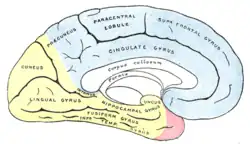

Nach dem Eintritt in den Schädel durch den Canalis caroticus zweigt aus der Arteria carotis interna jeder Seite ein Gefäß zum Auge (Arteria ophthalmica) ab. Nach Abgabe weiterer kleinerer Äste teilt sie sich in die Hauptstämme des vorderen Kreislaufs, die mittlere Hirnarterie (Arteria cerebri media) und die vordere Hirnarterie (Arteria cerebri anterior, bei Tieren als Arteria cerebri rostralis bezeichnet). Erstere versorgt die seitlichen (lateralen), letztere die der Mitte zugewandten (medialen) Teile der jeweiligen Großhirnhemisphäre mit Ausnahme von Teilen des Temporallappens und des gesamten Occipitallappens, die vom hinteren Kreislauf gespeist werden. Die tiefen Kerngebiete (Basalganglien, Thalamus) haben eine gemischte Versorgung. Die beiden vorderen Hirnarterien sind durch die sehr kurze Arteria communicans anterior miteinander verbunden.

Die Wirbelarterien in ihren Endsegmenten und die Arteria basilaris entsenden Äste zum Hirnstamm und Kleinhirn (A. cerebelli inferior posterior, A. cerebelli inferior anterior, A. cerebelli superior). Oberhalb der Brücke teilt sich die Arteria basilaris abermals und wird zu den beiden hinteren Hirnarterien, die sich in die Arteriae occipitales medialis bzw. lateralis teilen und die hinteren Bezirke des Großhirns sowie Teile des Zwischenhirns versorgen. Eine individuell unterschiedlich stark angelegte Arteria communicans posterior verbindet die hintere Hirnarterie jeder Seite mit der inneren Halsschlagader.

Versorgungsgebiete der Großhirnrinde: Arteria cerebri anterior (blau unterlegt) |